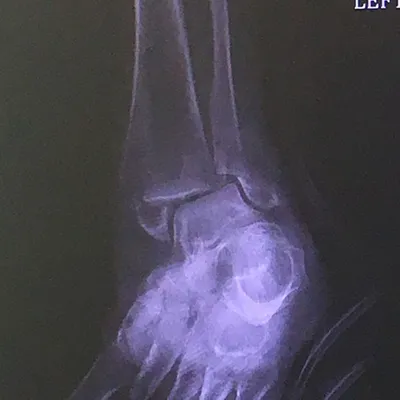

Preop and Postop Trimalleolar Fracture with Fixation of Posterior Malleolus Fracture

Preop

Postop